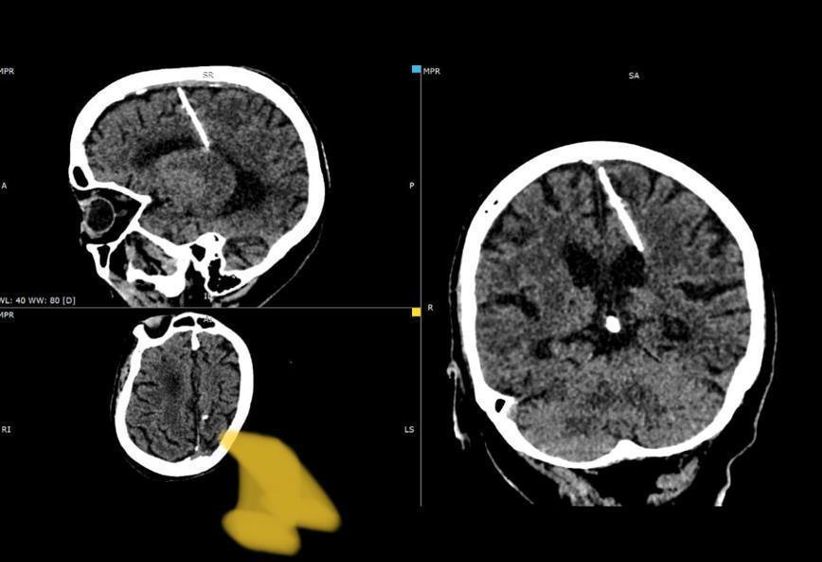

Трехсантиметровую иглу в мозге у 80-летней женщины выяила КТ.

Трехсантиметровую иглу в голове 80-летней жительницы Сахалина обнаружили врачи, сообщил в Telegram-канале региональный Минздрав.

Как отмечается, живет женщина с инородным телом с рождения. Проникла игла в левую теменную долю, но девочка выжила. Более того, ее в дальнейшем никогда не мучили головные боли.

Иглу увидели на снимках компьютерной томографии, пояснили в ведомстве.

Было решено не делать операцию, поскольку это может только ухудшить состояние пациентки.